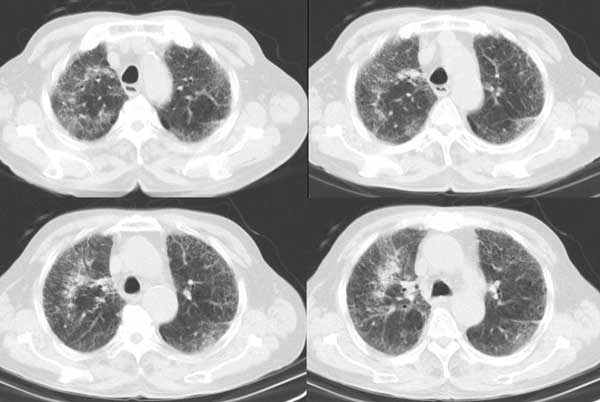

以下是引用同在2006-7-20 21:01:00的发言:[br]间质性肺炎,两肺纤维化,肺气肿。

以下是引用dalianren在2006-7-20 21:23:00的发言:[br]我考虑是肺泡蛋白沉积症:典型表现为两肺内散在片状\"磨玻璃\"样混浊区呈地图样分布.

以下是引用lj0804在2006-7-21 12:57:00的发言:[br]支持[br]我考虑是肺泡蛋白沉积症:典型表现为两肺内散在片状\"磨玻璃\"样混浊去呈地图样分布.